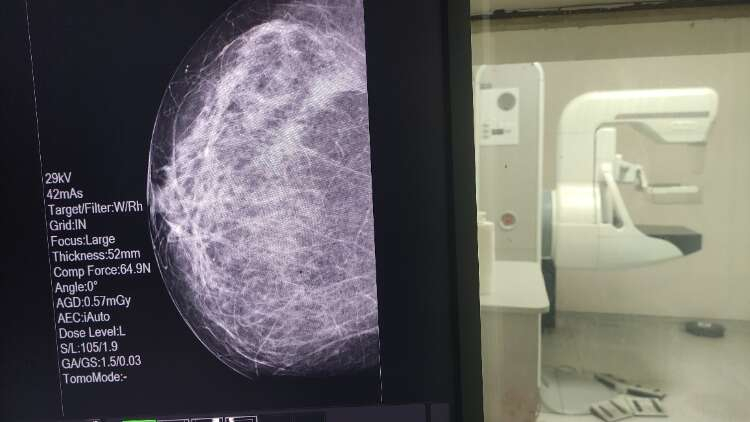

Tarama için ayırdığı 5 dakika hayatını kurtardı

Nilüfer İlçe Sağlık Müdürlüğü’ne bağlı sağlıklı hayat merkezinde görev yapan Dr. Mehlika Yavuz, erken teşhisin önemine kendinden örnek verdi. Yalnızca 5 dakika ayırıp çektirdiği mamografi sayesinde meme kanserinin erken evrede teşhis edildiğini vurgulayan Dr. Yavuz, o 5 dakikanın tüm hayatını etkileyen olumlu sonuçlara yol açtığını belirtti.